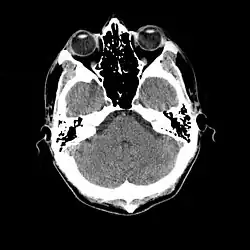

As imagens tomográficas podem ser obtidas em dois planos básicos: o plano axial (perpendicular ao maior eixo do corpo) e o plano coronal (paralelo a sutura coronal do crânio ou seja é uma visão frontal). Após obtidas as imagens, recursos computacionais podem permitir reconstruções no plano sagital (paralelo a sutura sagital do crânio) ou reconstruções tridimensionais.

O uso de diferentes janelas em tomografia permite por exemplo o estudo dos ossos com distinção entre a cortical e a medular óssea ou o estudo de partes moles com a distinção, por exemplo, no cérebro entre a substância branca e a cinzenta. A mesma imagem pode ser mostrada com diferentes ajustes da janela, de modo a mostrar diferentes estruturas de cada vez. Não é possível usar um só ajuste da janela para ver, por exemplo, detalhes ósseos e de tecido adiposo ao mesmo tempo.

Características das imagens tomográficas

Entre as características das imagens tomográficas destacam-se os pixeis, a matriz, o campo de visão (ou fov, em inglês: field of view), a escala de cinza e as janelas.[1]